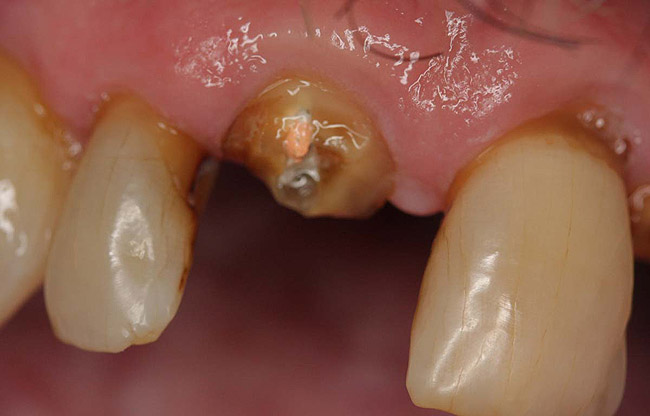

Figure 15  Fractured tooth in a crown of a recently treated endodontically central incisor.

Figure 15

Figure 16  The fractured central incisor root.

Figure 16

Case 4

A terminally ill patient presented an abscess on the maxillary right central incisor. Endodontic treatment was completed with a composite restoration placed to restore the access hole. The crown fractured off within 1 week (Figure 15 and Figure 16). Gutta-percha was removed, and the canal prepared to accept a C-1 white post (Figure 17). The root was bonded with BRUSH and BOND™ (Parkell, www.parkell.com) and the post was cemented with a resin cement (Figure 18). Absolute Dentin core build-up material was applied (Figure 19). There are many different build-up materials, including glass ionomers such as Ketac-Silver™ (3M ESPE, www.3mespe.com) or Miracle Mix® (GC America, www.gcamerica.com), pastes that are mixed such as Zenith (Carson Dental, www.carsondental.com), and automix syringes such as Absolute Dentin. The material was of a consistency that allows placement without sagging or running (Figure 20). It was light-cured and prepared for temporization (Figure 21) and the final all-composite restoration was delivered (Figure 22).